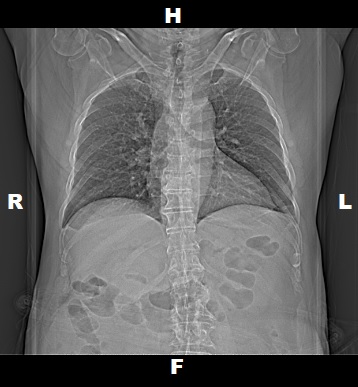

Topogram

• Position the patient in head first supine position.

• Align the patient in Mid-Sagittal plane of the table.

• Position the transverse laser light beam at the level of patient’s upper shoulder to start the topogram.

Topogram Parameters

• Topogram length: 512 mm

• Slice: 0.6 mm

• Scanning direction: Craniocoudal

• Tube position: Top

• Stop the topogram scanning when the scanning reach / pass over the iliac crest.